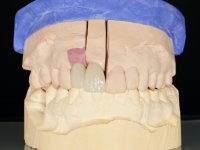

Segunda Fase.

Após 5 anos da primeira intervenção, a paciente surge na consulta com uma peri-implantite nos implantes colocados no local dos dentes 1.2 e 4.6. Começamos por abordar a peri-implantite no local do dente 2.2. Foi feita uma ponte provisória de laboratório em acrílico com 2 elementos. O dente 1.1 como pilar e o 1.2 como pôntico, este último apresentava um apoio distal. A coroa do 1.2 foi removida do coto com um corte longitudinal feito com turbina e depois foi fraturada com um mini luxador. O coto foi de seguida desaparafusado do implante. Fez-se o mesmo procedimento para remover a coroa do 1.1. O dente 1.1 foi re-preparado e a ponte provisória foi rebaseada em boca com acrílico autopolimerizável. Feito o correto acabamento e polimento da provisória foi feita a sua cimentação temporária com cimento de policarboxylato. Numa consulta posterior. foi feita a remoção da ponte provisória, feita a cirurgia para explantação do implante, colocou-se um novo implante e fez-se a regeneração óssea da zona com uma membrana não reabsorvível. 3 meses após foi removida a coroa do implante colocado no 4.6. Foi feito um corte horizontal com turbina na zona cervical e com um mini luxador descolou-se a coroa do coto. Após este procedimento fez-se a explantação do implante. Após 6 meses foi colocado um novo implante no local do 4.6. Após a osteointegração foi feita a impressão com a técnica de moldeira aberta e foi confecionada em laboratório uma coroa aparafusada sobre o implante. Aprovada pela paciente foi apertada definitivamente em boca. Após 1 mês removemos a ponte provisória antero-superior, reforçamos o dente 1.1 com um poste intra- radicular e reconstruimos o coto com uma resina de polimerização dual. Nessa mesma consulta expomos o implante colocado no 1.2 e fizemos uma impressão pela técnica de moldeira aberta com silicone de dupla viscosidade e presa rápida. No laboratório foi feita uma ponte provisória de 2 elementos, aparafusada sobre o implante e cimentada sobre o dente. A primeira ponte provisória foi removida e colocada a segunda aparafusada sobre o implante. A linha de acabamento cervical do 1.1 foi rebaseada com resina composta durante o aperto do parafuso do implante. Depois foi removida, foram feitos os acabamentos e finalmente apertada sobre o implante e cimentada temporariamente sobre o dente. Após 2 meses de maturação dos tecidos moles em função do perfil de emergência criado pela nova ponte provisória, pudemos avaliar a estética conseguida em conjunto com a paciente. Neste longo processo o dente 2.1 teve que fazer um tratamento endodôntico. Decidiu-se assim fazer também uma coroa no dente 2.1.O dente 2.1 foi preparado na mesma consulta em que se fez a impressão ao implante. A ponte provisória foi utilizada para individualizar a peça de transferência, copiando o seu perfil de emergência e em seguida foi realizado o afastamento gengival com caolino. A impressão foi feita com a técnica de moldeira aberta com silicone de dupla viscosidade e presa rápida. Após a escolha da cor, a impressão foi enviada  para o laboratório onde foram confecionadas 2 coroas  com infraestrutura em Zr. revestidas a cerâmica para os dentes 1.1 e 2.1 e uma coroa aparafusada sobre o implante no dente 1.2. O trabalho final foi aprovado pela paciente e foi colocado definitivamente em boca. A coroa sobre o implante foi aparafusada com 35 N e as coroas foram cimentadas com cimento de ionómero de vidro reforçado com resina.